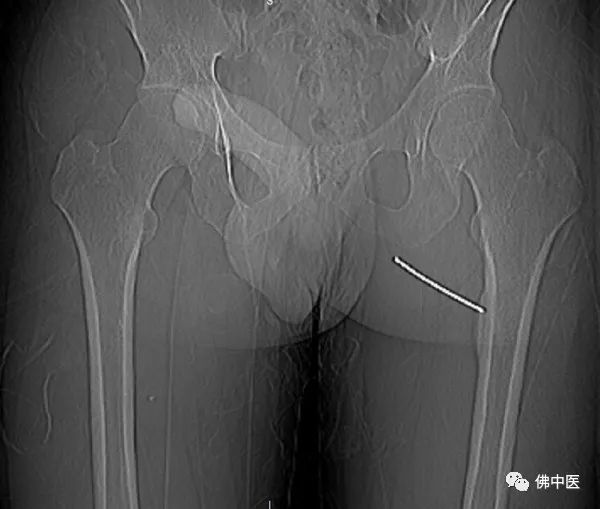

术中,射频针直击病灶

小陆右腿检查片

术中,影像引导射频穿刺